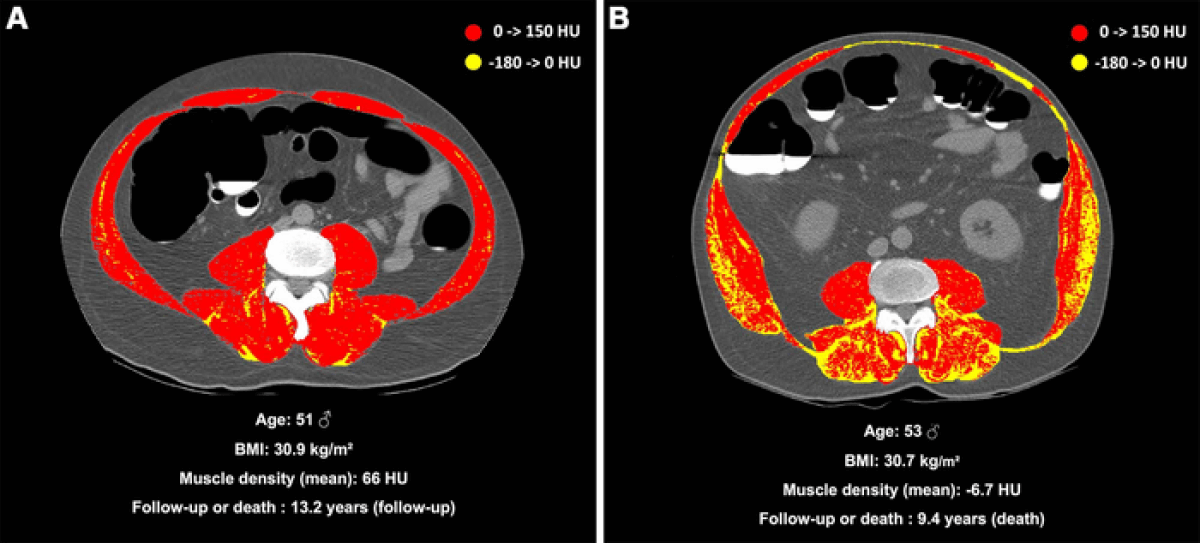

A study involving nearly 9,000 adults revealed a 10-year mortality risk of 15.5 percent for those with myosteatosis, compared to 7.6 percent for obese individuals. This risk even surpassed factors like fat around abdominal organs, fatty liver disease, and was comparable to risks associated with smoking or having Type 2 diabetes. Despite mounting evidence of its danger, myosteatosis remains largely overlooked in the medical community.

“Interestingly, the correlation was independent of age or obesity indicators such as BMI,” says study co-author Dr. Maxime Nachit in a media release. “This suggests that muscle fat accumulation is not simply a result of aging or having excessive fat in other body areas.”

Physicians often use the Body Mass Index (BMI) to estimate a patient’s body fat. However, since BMI is calculated based on a patient’s height and weight, it doesn’t accurately reflect body composition. Individuals with similar BMIs can have significantly different health risks and co-morbidities. Future research could clarify whether myosteatosis merely indicates poorer health status or if it directly contributes to an increased risk of death.

To address this, the researchers utilized artificial intelligence, specifically machine learning, to extract body composition metrics from abdominal CT scans of asymptomatic adults who underwent routine bowel cancer screenings between 2004 and 2016. The study recorded major adverse events, such as heart attacks, strokes, aneurysms, and deaths. Myosteatosis was identified in 55 percent of the 507 participants who died during the average follow-up period of almost nine years.